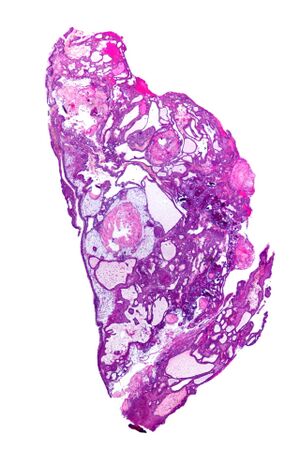

Adamantinomatous craniopharyngioma - very low mag.jpg

Very low magnification micrograph of an adamantinomatous craniopharyngioma. HPS stain.

في بعض الحالات ، يمكن أن يساعد ماسح التصوير بالرنين المغناطيسي القوي 3T (Tesla) في تحديد موقع هياكل الدماغ الهامة المتأثرة بالورم. يتكون النمط النسيجي من تعشيش ظهارة حرشفية تحدها خلايا مرتبة بشكل اشعاعي. غالبًا ما يكون مصحوبًا بترسب الكالسيوم وقد يكون له بنية حليمية مجهرية. يعد التصوير المقطعي المحوسب (CT) أيضًا أداة تشخيصية جيدة ، حيث يكتشف التكلس في الورم..[20]

في الفحص العياني ، يكون الورم القحفي البلعومي كيسيًا أو كيسيًا جزئيًا مع مناطق صلبة. في المجهر الضوئي ، يُنظر إلى الأكياس على أنها مبطنة بظهارة حرشفية طبقية. يمكن أيضًا رؤية لآلئ الكيراتين. تمتلئ الأكياس عادة بسائل أصفر لزج غني ببلورات الكوليسترول. من بين قائمة طويلة من الأعراض المحتملة ، تشمل العروض المجيئية الأكثر شيوعًا الصداع ، وفشل النمو ، والعمى نصفي صدغي مزدوج .